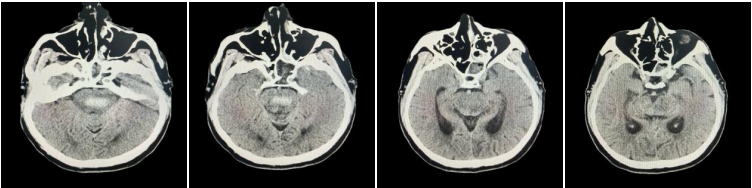

近日,我院成功救治一名 54 岁突发脑干出血患者。该患者因「突发意识不清 2 小时」被紧急送至我院,急诊科团队迅速启动卒中绿色通道,经头颅 CT 检查,确诊为脑干出血约 3 ml。由于脑干位置特殊、功能关键,脑干出血被称为神经外科的「手术禁区」,治疗过程中每一步都关乎生死。

在积极控制血压、给予止血药物治疗后,患者复查头颅 CT 显示出血量增加至 7 ml,病情进一步加重。医疗团队综合评估认为,脑干区域手术风险极高,经与家属充分沟通,最终决定实施个体化保守治疗方案。同时,医院立即组织呼吸科、麻醉科等多学科专家进行联合会诊,共同制定精准、系统的救治策略。